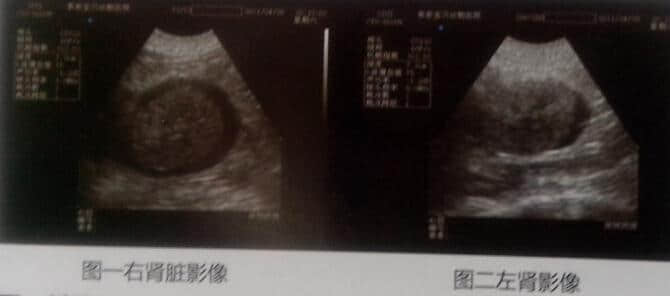

四、影像学检查:B超检查:双肾囊肿、被膜下积液。

(1)结膜炎(2)双肾周囊肿被膜下积液引起慢性肾衰